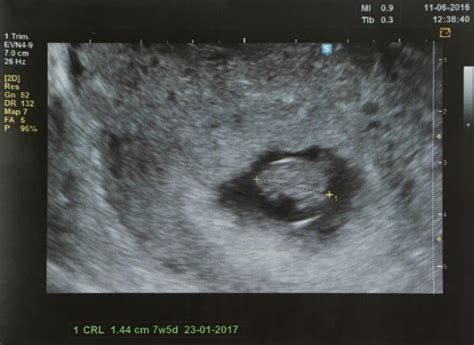

Vârsta gestațională

Dacă ești însărcinată în mai puțin de 7 săptămâni, este puțin probabil să auzi bătăile inimii la ecografie. La ecografiile transvaginale, bătăile inimii unui făt ar trebui să fie clar vizibile până la momentul în care o femeie este însărcinată în 7 săptămâni. Ecografia abdominală este considerabil mai puțin sensibilă, așa că poate dura mai mult până când bătăile inimii devin vizibile.

La 5 săptămâni de sarcină, embrionul măsoară în jur de 2 mm, iar sistemul său nervos se dezvoltă deja. Se dezvoltă, de asemenea, inima și primele vase de sânge ale embrionului de 5 săptămâni, din care se va forma cordonul ombilical. Majoritatea femeilor conștientizează abia acum că ar putea fi însărcinate, când sarcina e în săptămâna 5. Contactează medicul obstetrician pentru o primă programare de confirmare a sarcinii și pentru a primi recomandări de îngrijire prenatală. Dacă nu ai început deja, în săptămâna 5 de sarcină ia un supliment de acid folic de 400 mg pe zi. Când vine vorba despre sarcină, săptămâna 6 este marcată de obicei de ecografia de confirmare a sarcinii, când vei putea probabil să auzi pentru prima oară inima viitorului tău copil.

În săptămâna 7 de sarcină embrionul a ajuns la aproximativ 10 mm lungime, din vârful capului până în zona șezutului. Creierul se dezvoltă rapid, ceea ce face ca și creșterea capului să fie accelerată. Începând cu săptămâna 8 de sarcină viitorul bebeluș este denumit fetus. Picioarele i se lungesc, chiar dacă diferitele segmente ale membrelor nu sunt, încă, distincte. Placenta continuă să se formeze, pregătindu-se să se atașeze de peretele uterin.